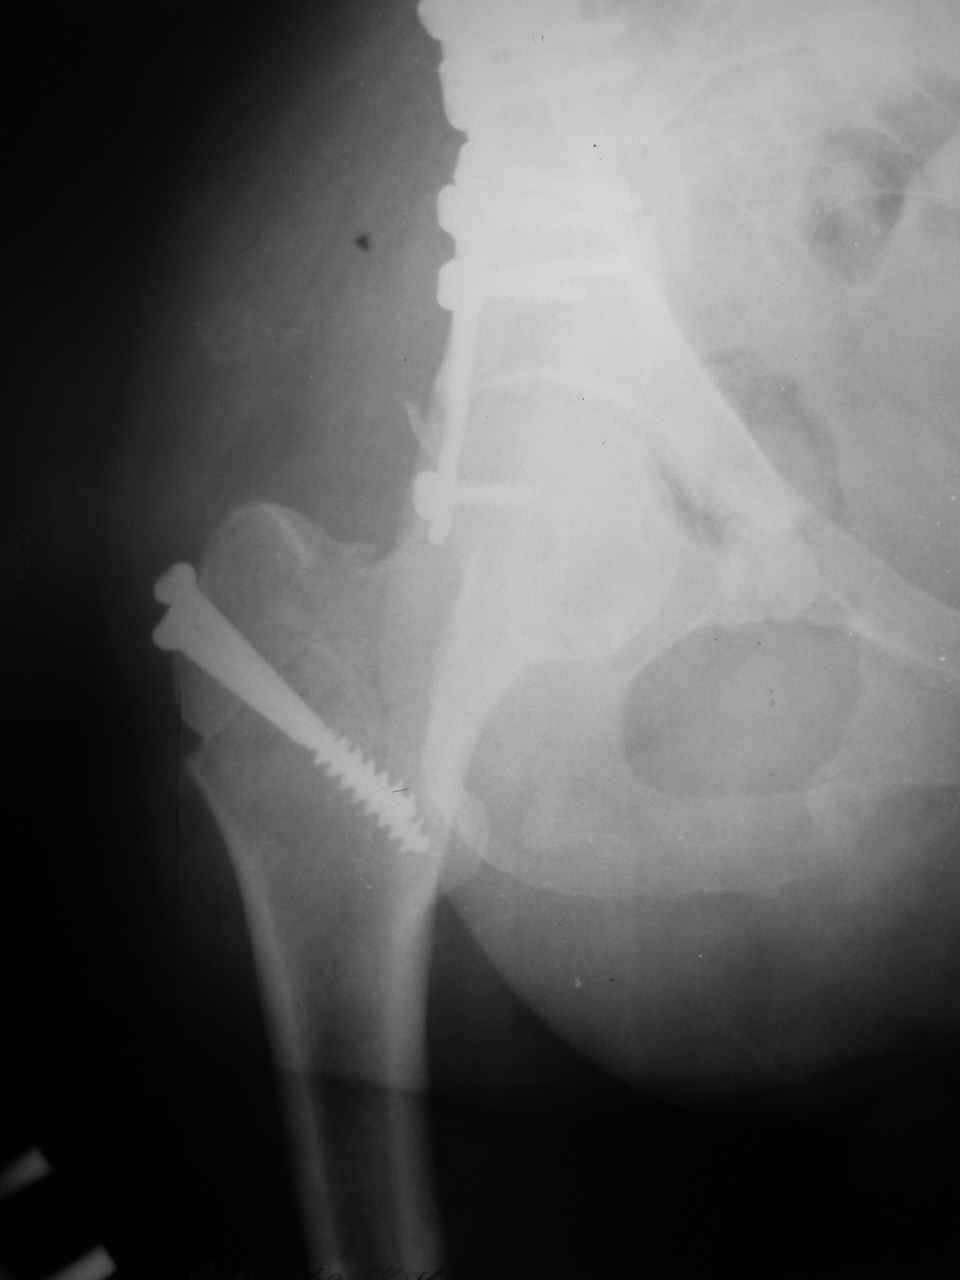

Интерес к реконструкции вертлужной впадины у меня появился довольно-таки давно, но до недавнего времени как-то не ощущалась готовность к практической реализации, а местный подход достаточно консервативен - перелом срастется,

а далее будет видно. Такую точку зрения я не разделяю, поэтому через конференции,ортофорум и свои случаи пытаюсь практически и теоретически *продвинуть* для себя тему реконструкции вертлужной впадины.

Логика подсказывает, что все-таки лучше иметь анатомически полноценную впадину, хотя ранее упоминалось состояние вторичной конгруэнтности и одно наблюдение у меня есть, когда у больного с полностью нарушенной анатомией впадины и подвывихом головки бедра кзади и кверху боли отсутствовали при относительно достаточном для стиля жизни больного объёме движений. Но это только одно наблюдение и кроме перелома впадины у этогобольного была и тяжелая ЧМТ в анамнезе. Основываясь на формулировке структуры ацетабулюм Э. Летурнеля - как перевернутой буквы Y, впадина для полноценной функции сустава должна иметь сферичность, соответствующую размеру головки бедра и если один из компонентов в дефиците, то функциональные последствия рано или поздно проявятся.

Сложностью, ассоциативностью характера перелома, я бы с радостью воспользовался мининвазивной перкутанной фиксацией винтами, но боюсь, что результат был бы ещё хуже, техникой непрямой репозиции перелома не владею, поэтому пытаясь получить анатомичную впадину приходится широко открывать, по крайней мере пока, а дальше буду пытаться уменьшать пространство...

Илеофеморальный доступ не совсем передний и сравнительно с илеоингвинальным, и Кохера-Лангенбека открывает весь наружный таз кроме самых передних отделов лонных костей, фиксацию которых я не ставил в задачу. Обширность диссекции, большая длительность операции и более высокий риск гетерооссификации - отрицательные моменты в обмен на возможность легче ориентироваться.